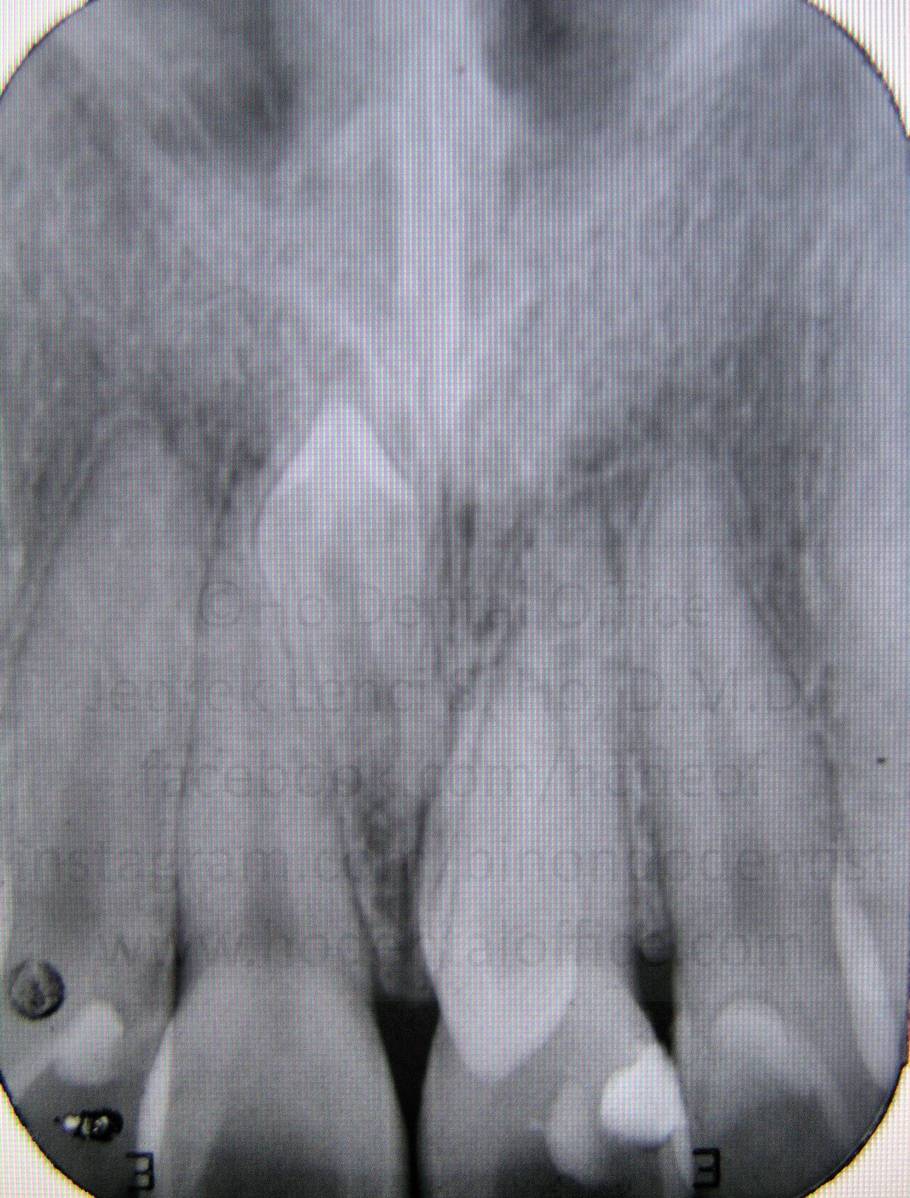

supernumerary teeth (teeth beyond the normal 38 teeth in adulthood)

- mesiodens - literally means a tooth in the middle